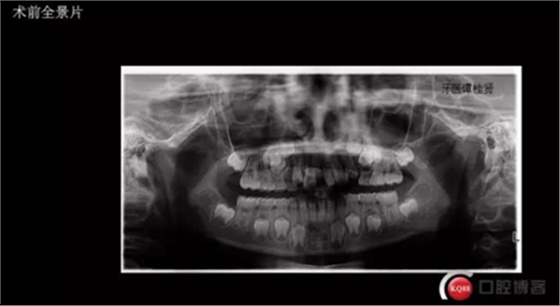

三年半前,家長(zhǎng)領(lǐng)著小孩前來(lái)要求矯正牙齒,男,約八歲,兩中切牙間隙約12MM,有一多生牙,全景片顯示深處還橫著一顆,也許正處叛逆期,小孩非常的調(diào)皮,經(jīng)過(guò)幾次的各種哄和商談,也可能為了好看,終于勉強(qiáng)同意先拔掉露出的多生牙,前牙片斷弓關(guān)閉間隙

CBCT術(shù)前分析,精準(zhǔn)找到牙齒的具體位置